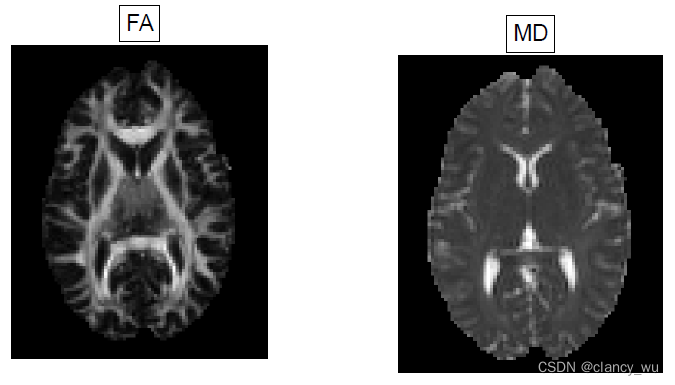

如下图:

不同场景对FA,MD的影响

细胞肿胀:

FA↑,MD↓

髓鞘丢失:

FA↓,MD↑

细胞死亡:

FA↓,MD↑

这个也很好理解,结合上述原理就能理解。值得注意的是,FSL特别强调,这只是可能的几种解释情况,但是实际情况很复杂,所以不要过度解读。